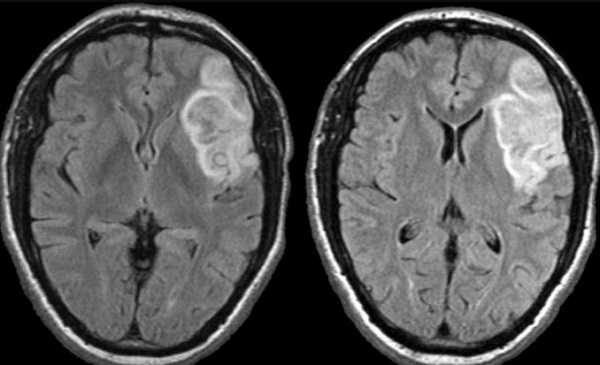

На нижележащих изображениях слева представлена диффузно-взвешенное изображение, на котором возможно выявить ишемизированную ткань. Среднее изображение соответствует мр- перфузии, на котором визуализируется огромная область гипоперфузии. На крайне правом изображении diffusion-perfusion mismatch визуализируется зона ткани-риска, которая отмечена синим и возможно будет сохранена после терапии.